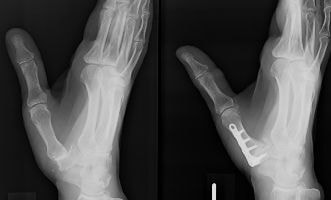

マレット変形

スワンネック変形

末節骨裂離骨折の経皮ピンニング

槌指とは木槌(マレット)のように変形した指を指す言葉であり、これには、末節骨の伸筋腱が付着する部位の裂離骨折によっておこるものと、伸筋腱の終止腱の断裂によっておこるものが含まれます。

いずれの場合も、症状はDIP関節の自動伸展障害ですが、放置するとスワンネック変形(白鳥の首様の変形)を生じます。さらに、骨折の場合には早期にDIP関節の変形性関節症を生じる原因となることがあります。

治療は、骨折があれば骨片の整復・固定を行うことで良好な結果が得られます。腱断裂の場合には2ヶ月間の外固定により4割の指に良好な結果が得られますが、6割の指には様々な程度(5〜20°)のDIP関節伸展障害が残存します。結果は、どれだけ早期に固定を開始できたか?と、どれだけしっかりとDIP関節の伸展位固定を維持できたか?にかかっており、ただ単に固定していたら治る、というものではありません。

陳旧例で骨の変形癒合がある場合には、骨切術により変形の矯正が可能です。腱断裂の陳旧例では、手術による腱の縫縮あるいは腱移行術によって変形の矯正が図られます。